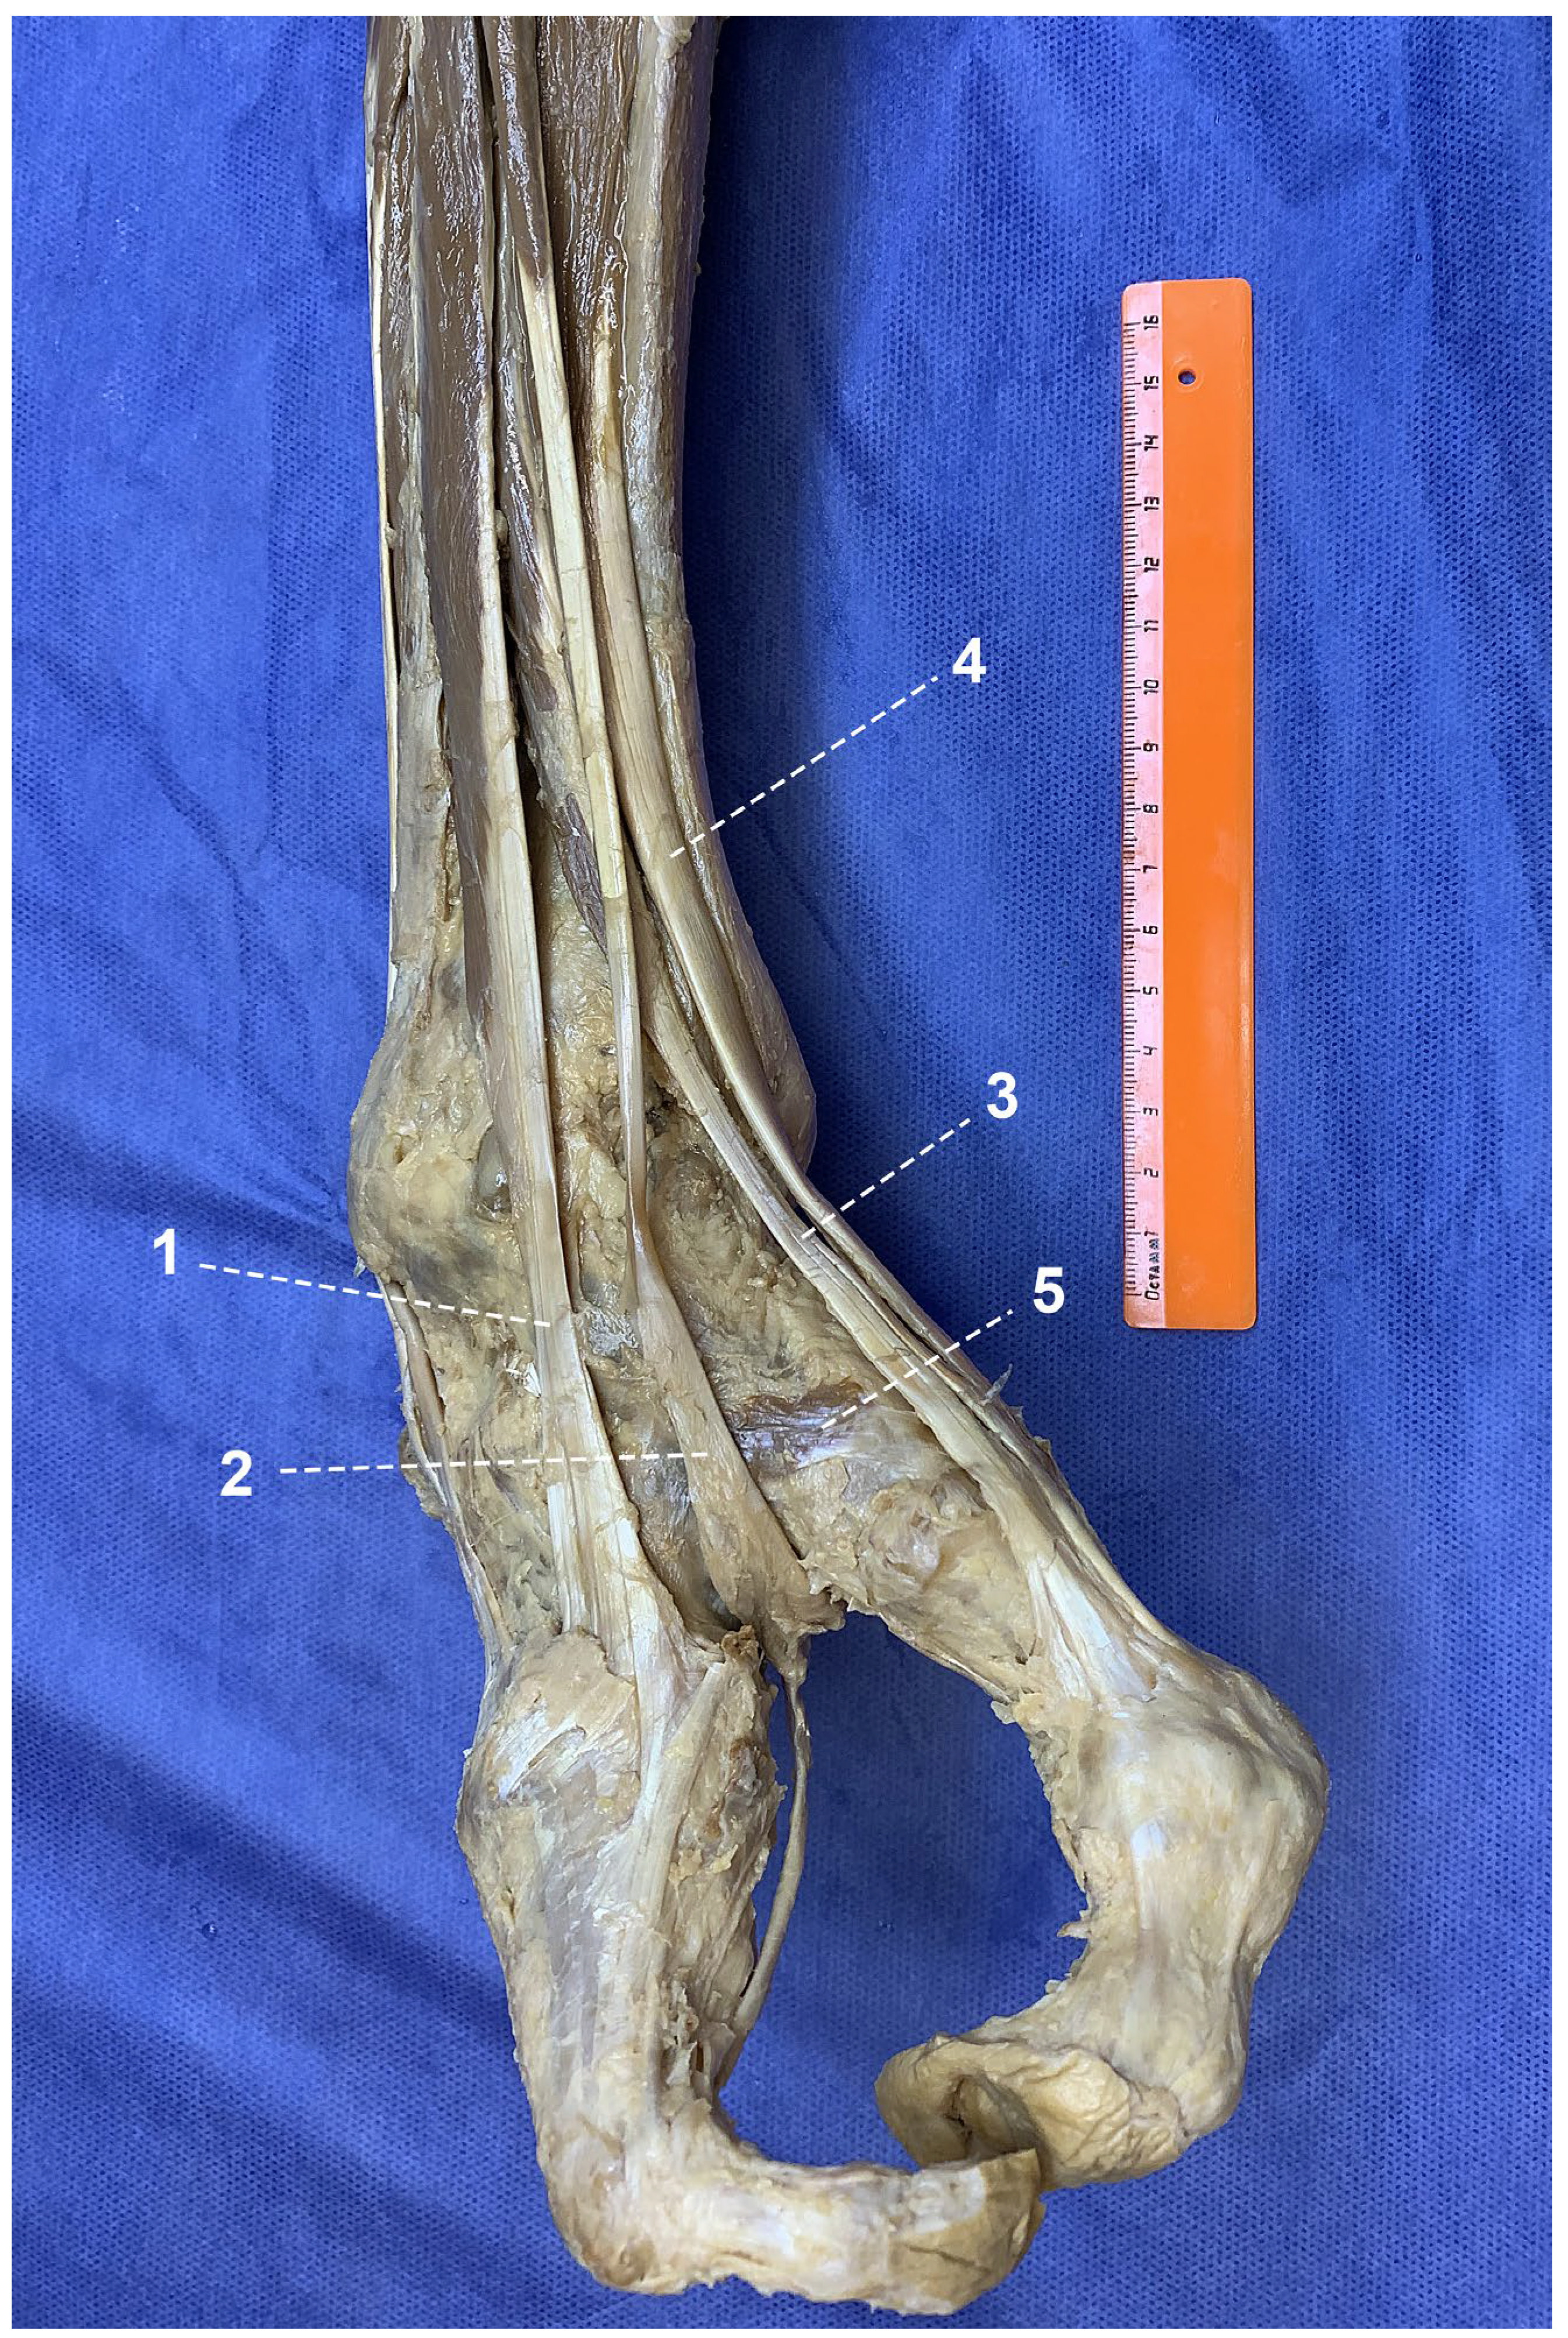

Figure 3. Attachment of peroneal tendons to the foot: 1—peroneus longus; 2—peroneus brevis; 3—lateral part of extensor digitorum longus; 4—Achilles tendon; 5—medial part of extensor digitorum longus; 6—extensor hallucis longus.

Within the lateral compartment, the peroneus longus tendon was shortened and inserted into the cuboid bone. The tendon of the peroneus brevis exhibited bifurcation: a broader and shorter branch inserted into the base of the fifth (lateral) metatarsal, whereas a longer and narrower branch continued distally onto the dorsal surface of the lateral ray (Figure 3).